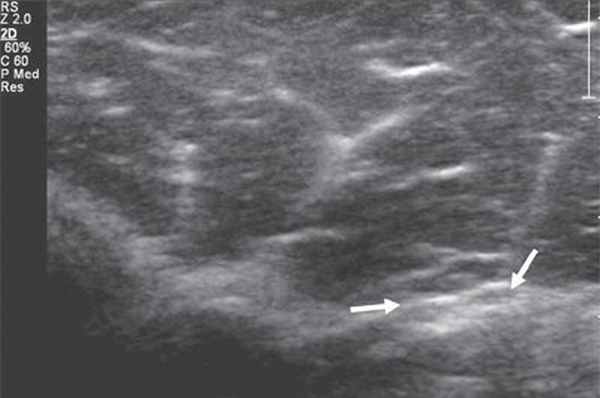

Срединный нерв формируется из латерального и медиального пучков плечевого сплетения. На плече n. medianus располагается в медиальной бороздке двуглавой мышцы кпереди от плечевой артерии. Срединный нерв является самым крупным нервом верхней конечности, поэтому его визуализация не представляет сложностей, однако легче всего можно получить ультразвуковое изображение нерва в области карпального канала, где он расположен поверхностно, а также на уровне локтевого сустава. В последнем случае в качестве маркера целесообразно использовать сосудистый пучок. В области локтевого сустава срединный нерв располагается медиальнее по отношению к более глубоко расположенным плечевой артерии и вене (рис. 3).

Рис. 3. Срединный нерв на уровне локтевого сустава в поперечной проекции (короткие стрелки). Рядом визуализируется плечевая артерия (длинная стрелка).